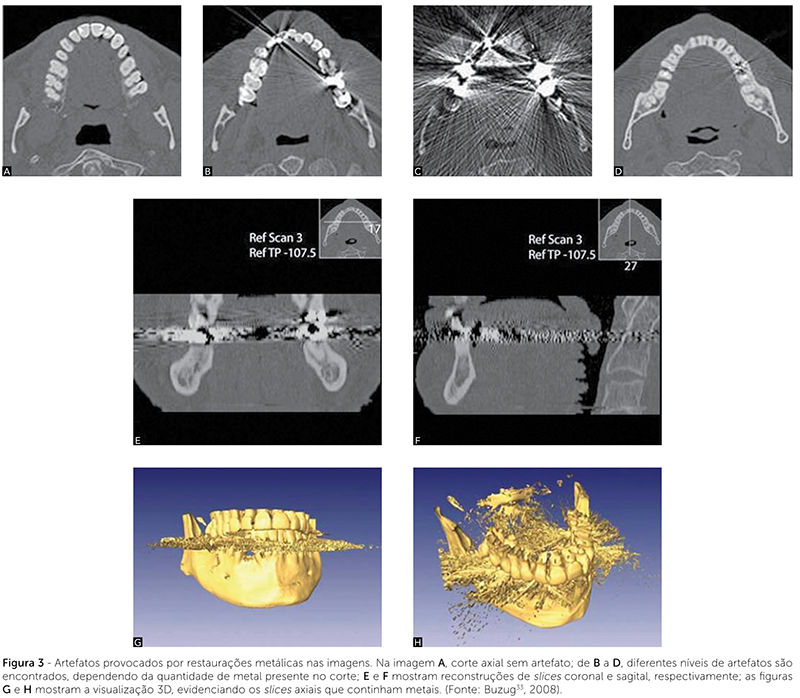

Quando o paciente possui restaurações metálicas ou faz uso de aparelho ortodôntico metálico no momento do exame, uma certa quantidade de artefatos interfere na qualidade da imagem obtida (Fig. 3). Isso foi uma desvantagem marcante para que o tomógrafo fan beam (feixes em leque) não se difundisse no meio odontológico14,28.